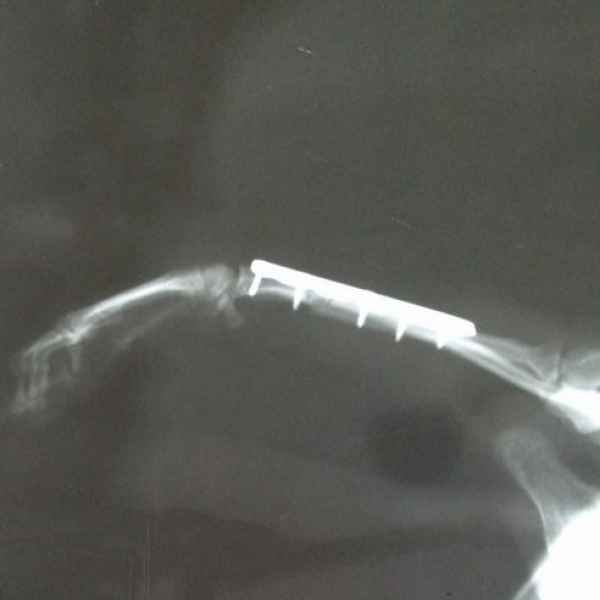

Вот что значит неудачно спрыгнуть с дивана. Это рентгеновские снимки одного из наших пациентов. Сначала хозяева обратили внимание на хромоту, а потом поняли, что у питомца очень болит лапа. Ещё бы не болело - поперечный перелом костей предплечья. Операция, установка DCP-пластины, восстановление, и он снова активный и жизнерадостный.